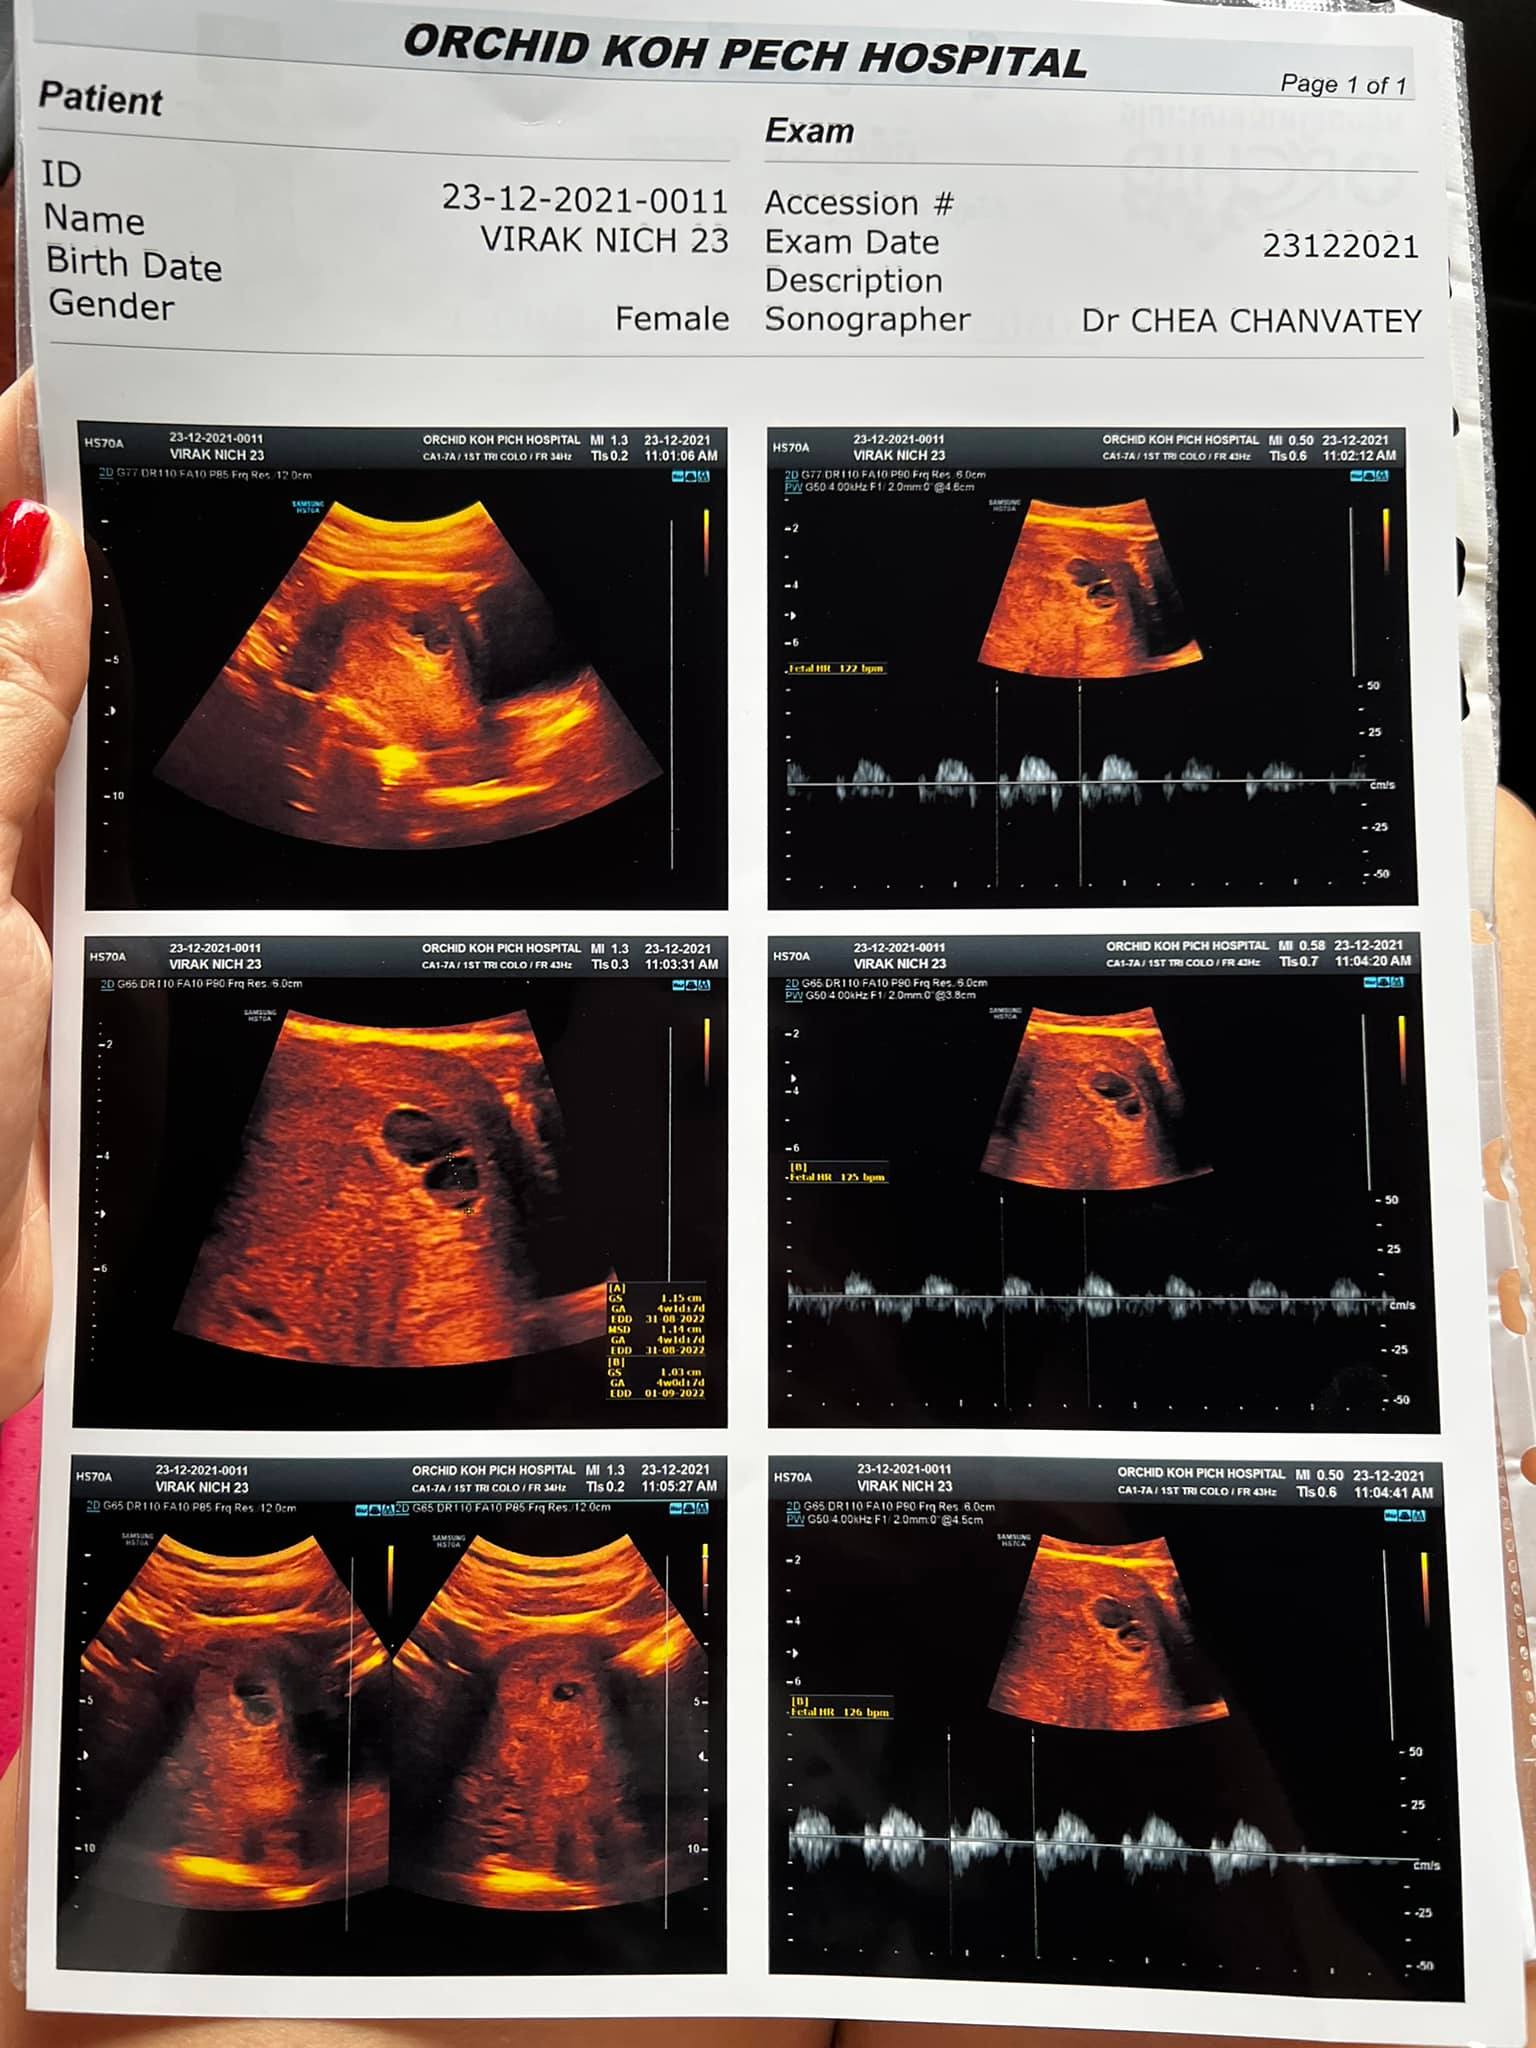

តារាចម្រៀងស្រីវ័យក្មេងល្បីឈ្មោះប្រចាំផលិតកម្មសាន់ដេ គឺអ្នកនាង វីរៈ និច្ច បានរៀបអាពាហ៍ពិពាហ៍ជាមួយនឹងលោក ខៀវ ពេជ្រ កាលពីថ្ងៃទី១៦ ខែតុលា ឆ្នាំ២០២១ កន្លងទៅនេះដោយរៀបចំឡើងនៅភោជនីយដ្ឋានមីងផាលេស។ ក្រោយរៀបការបានប្រមាណជាង២ខែ តារាស្រីរូបនេះបានបង្ហោះសារលាយឡំជាមួយអារម្មណ៍រំភើបយ៉ាងខ្លាំង ក្រោយទទួលបានដំណឹងថាខ្លួនពរពោះបានកូនភ្លោះ ដែលជាកូនដំបូងរបស់នាង។

អ្នកនាង វីរៈ និច្ច បានរៀបរាប់ថា៖ “23/12/2021 នេះជាកាដូធំបំផុតសំរាប់គ្រួសាររបស់ខ្ញុំ មិនមែន1ទេគឺទទួលបានសមាជិកថ្មីរហូតទៅដល់ 2 (ភ្លោះ) គ្មានពាក្យនិយាយអ្វីទេគឺរំភេីបខ្លាំងណាស់ Surprise ខ្លាំងមែនទែន អារម្មណ៍នេះមិនដែរបានទទួលពីមុនមកទេ រឿងដែរនឹកស្មានមិនដល់បែបនេះ Welcome New year 2022 #Mommy7week2days”